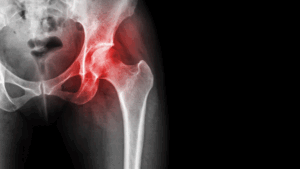

Partial Hip Replacement, also known as Hip Hemiarthroplasty, is a surgical procedure where only one part of the hip joint is replaced. Typically, this procedure involves replacing the femoral head (the ball of the hip joint) with a prosthetic component while leaving the acetabulum (the socket) intact. This surgery is often recommended for patients with a hip fracture, osteoarthritis, or avascular necrosis affecting only the femoral head, allowing them to retain the rest of the joint structure.

Hip Fractures

Traumatic fractures or fractures due to conditions like osteoporosis can necessitate a partial hip replacement, particularly if the femoral head is damaged

Avascular Necrosis

- X-Rays: X-rays are essential for evaluating the damage to the hip joint and determining the need for surgery. They can show the extent of wear on the joint and identify fractures.